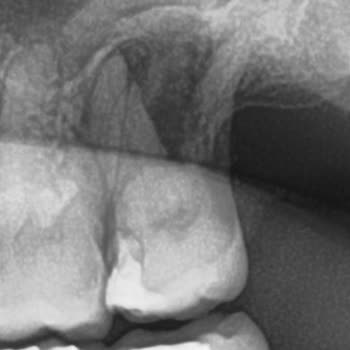

Hospitadent Pendik şubesinde 11 Şubat’ta sağ taraftaki azı dişime dolgu yaptırdım. Bu işlemden yaklaşık iki ay sonra dolgudan ufak bir parça koptu ve 10 Nisan’dan beri o dişimde tek taraflı, nabız gibi atan bir sızı ve belirgin hassasiyet yaşıyorum. Daha önce bu dişimle ilgili hiçbir şikayetim yokken rahatça çiğneme yapabiliyordum, dolgunun kırılmasıyla birlikte sıcak‑soğuk temasında ve çiğneme sırasında sürekli rahatsızlık hissediyorum.

Şikayetlerim üzerine kliniğe tekrar gittiğimde doktor, dişimde bir sorun olmadığını söyleyip sadece florür verniği uyguladı ve evde kullanmam için bir tane verdi. Ancak ağrı ve diş hassasiyetinde hiçbir düzelme olmadı, günlük hayatımı etkileyen bu sorun aynı şekilde devam ediyor. Ufacık bir parça bile kopmuş olsa bunun “bir şey olmaz” denilerek geçiştirilecek bir durum olmadığını, dişimin ileride daha ciddi sorunlar çıkarıp yaşam kalitemi düşürmesinden endişe duyduğumu belirtmek istiyorum.

Buna ek olarak, başka bir hekim 18 Şubat’ta sol taraftaki azı dişlerime dolgu yaparken çürük olmayan sağlam dişimi de şüphe duyup açtı ve dişimin şeklini bozdu. Bu dişim dilime takılmaya, dilimi rahatsız etmeye başladı. Bu nedenle kliniğe üç kez daha gitmek zorunda kaldım ve her seferinde sadece törpüleme işlemi yapıldı, dişim iyice formunu kaybetti. Ücret ödeyerek hizmet aldığım bir klinikte bu sorunlarla baş başa bırakılmak bir hasta ve müşteri olarak beni hayal kırıklığına uğrattı.

Başta dolguların beş yıl garantili olduğu özellikle belirtilmişken, yaşadığım mağduriyetle ilgili olarak öncelikle tarafıma bir özür ve açıklama yapılmasını, ardından da dişlerimle ilgili gerekli tüm düzeltici işlemlerin garanti kapsamında ek ücret talep edilmeden, kalıcı şekilde yapılmasını talep ediyorum.